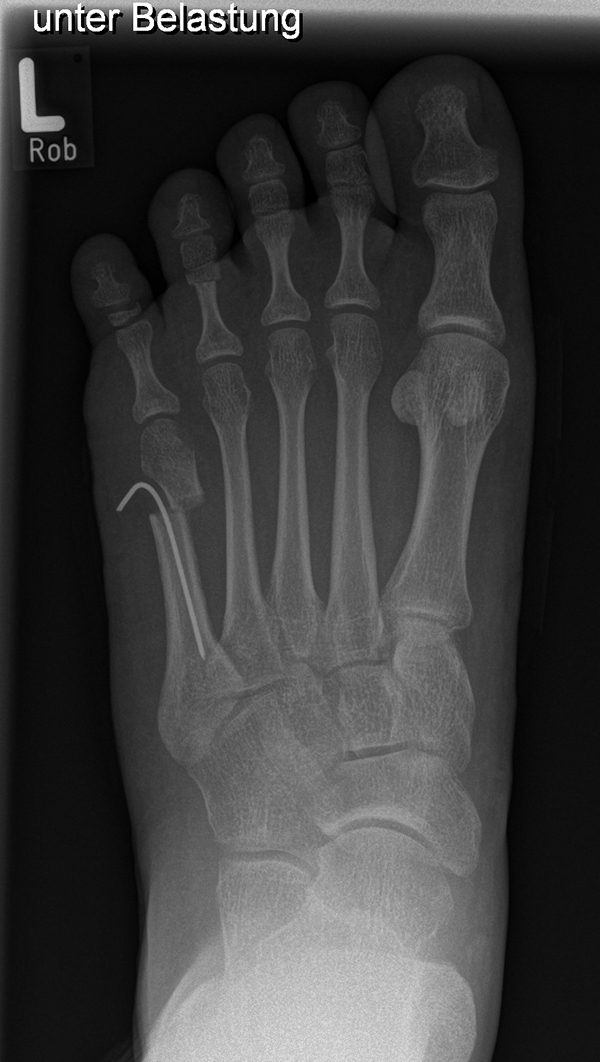

Knick-Senk-Platt-Fuß Korrektur mit dem Canalis Tarsi Spacer

In der Korrektur des schmerzhaften, aber flexiblen Knick-Senk-Fußes oder Plattfußes ist die Schraubenarthrorise mit einem Sinus tarsi oder besser bezeichnet als Canalis tarsi Spacer und alternativ mit einer Calcaneus-Stopp-Schraube seit vielen Jahren ein etabliertes Verfahren und führt zu einer kompletten Korrektur von flexiblen Knick- und Plattfuß-Fehlstellungen (Abb. 7). Die nötige Schnittlänge über dem Sinus tarsi beträgt für beide Verfahren 1 cm.

Abb. 7 a-e: Knick-Senk-Fuß prä- und postoperative Situation (a-b), ventrale und dorsale Ansicht (c-d). Laterale Ansicht des Hautschnittes über dem Sinus tarsi (e).